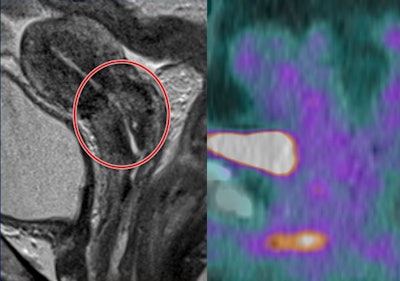

40-year-old LACC patient with stage B disease, node negative. Indeterminate residual T2-weighted signal change post CRT -- grade 3 (moderate response).

40-year-old LACC patient with stage B disease, node negative. Indeterminate residual T2-weighted signal change post CRT -- grade 3 (moderate response). Indeterminate residual T2-weighted signal change post CRT -- grade 3. No corresponding residual metabolic activity on PET/CT -- grade 1 (complete metabolic response). Patient remains disease-free three years later.

Indeterminate residual T2-weighted signal change post CRT -- grade 3. No corresponding residual metabolic activity on PET/CT -- grade 1 (complete metabolic response). Patient remains disease-free three years later."Our current work is focused on evaluating whether extracting novel (quantitative) features -- including metabolic tumour volume and standardized uptake value metrics derived from FDG-PET/CT as well as radiomic features along with quantitative feature analysis of MRI -- has a greater ability to predict patient outcome when compared to qualitative analysis," he told AuntMinnieEurope.com.